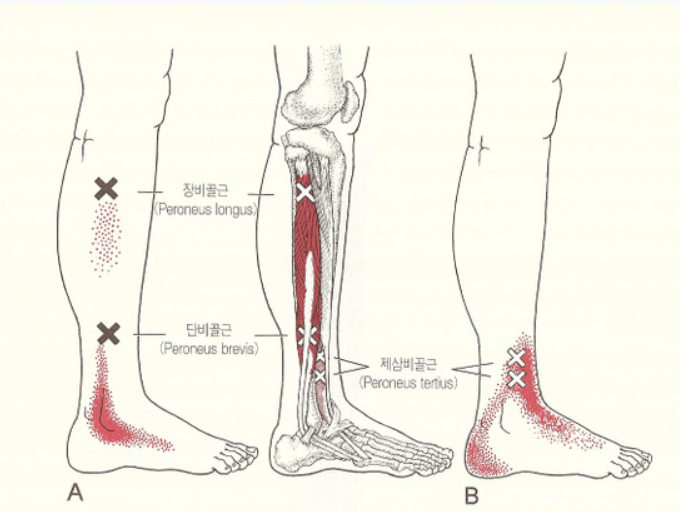

5. 아킬레스건염 (Achilles Tendinitis)

- 원인: 발뒤꿈치와 종아리를 연결하는 아킬레스건에 염증이 발생.

- 특징: 발뒤꿈치 후방 통증, 발목을 굽히거나 펴면 악화.

- 위험 요인: 과도한 러닝, 점프 운동, 종아리 근육 뻣뻣함.

- 대처법: 스트레칭, 휴식, 물리치료.